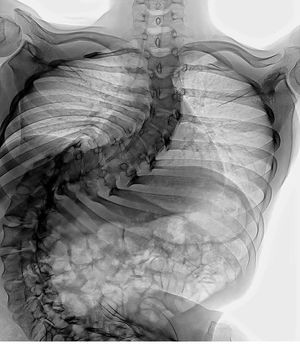

Scoliosis

Not just scoliosis WORST scoliosis everđ

Scoliosis right?